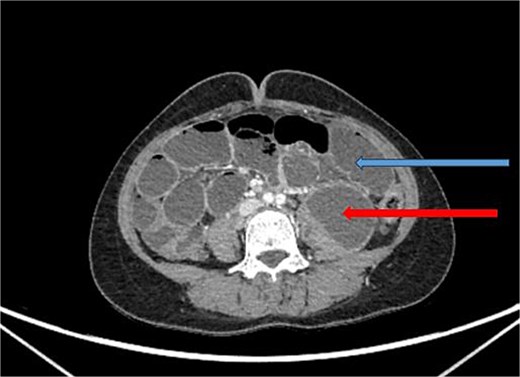

X-ray abdomen showed dilated small bowel loops with faecal loading (Fig. 1). Ultrasound abdomen/pelvis revealed dilated small bowel loops with to-and-fro peristalsis, suggestive of small bowel obstruction. Contrast-enhanced computed tomography (CT) abdomen/pelvis revealed distal ileal thickening causing obstruction, a left iliopsoas abscess communicating with a paravertebral abscess (L5–S2), and erosion of the L5 vertebral body (Figs 2 and 3).

CT abdomen/pelvis with contrast, upper arrow showing dilated small bowel loops and lower arrow showing collection in left psoas muscle.